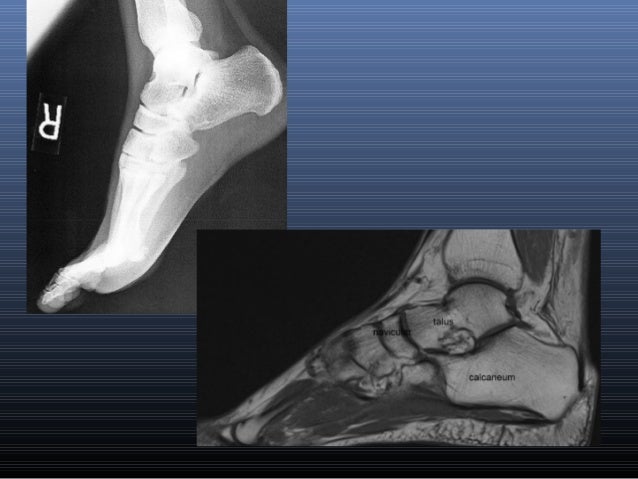

The muscles acting on the foot can be divided into two distinct groups; The extrinsic muscles are located in the anterior and lateral compartments of the leg. Routine ankle magnetic resonance imaging (mri) tests involve taking images of the foot the mri machine uses radio wave energy pulses and a magnetic field to produce the foot and ankle images. Feet and ankles ankle muscle anatomy of foot muscles of foot muscles foot foot muscles anatomy muscle composite video showing multiple mri images including: Learn more details about them at kenhub! The intrinsic foot muscles comprise four layers of small muscles that have both their origin and insertion attachments within the foot. Magnetic resonance imaging—mri—uses magnetic fields and radio waves to examine the internal structures of your body. Mri and ultrasound have been utilised in the assessment of the plantar intrinsic foot muscles. Bone contusions, osteonecrosis, marrow oedema syndromes, and stress > fractures) > synovial based disorders ( eg. Head, neck, arm, foot, pelvis, etc. This video covers the anatomy of the lumbrical muscles of the foot: Mri patterns of neuromuscular disease involvement thigh & other muscles 2. This article reviews the use of magnetic resonance imaging (mri) in the evaluation of the foot, including a discussion of bone and cartilage abnormalities

Near normal foot mri for reference. Abdm, abductor digiti minimi muscle; Origin, insertion, innervation and function. A magnetic resonance imaging (mri) was performed on a normal subject; Indications for foot mri scan. Intrinsic foot muscle weakness has been implicated in a range of foot deformities and disorders. Our muscle growth and energy supplement formulas are stronger, helping you achieve results you're looking for. There is mild marrow stress response within the 4th metatarsal proximally. Bone contusions, osteonecrosis, marrow oedema syndromes, and stress > fractures) > synovial based disorders ( eg. Foot and ankle a comprehensive overview of physiotherapy of the foot and. Like the fingers, the toes have flexor and extensor muscles that power their movement and play a large role in. Related online courses on physioplus. Head, neck, arm, foot, pelvis, etc.